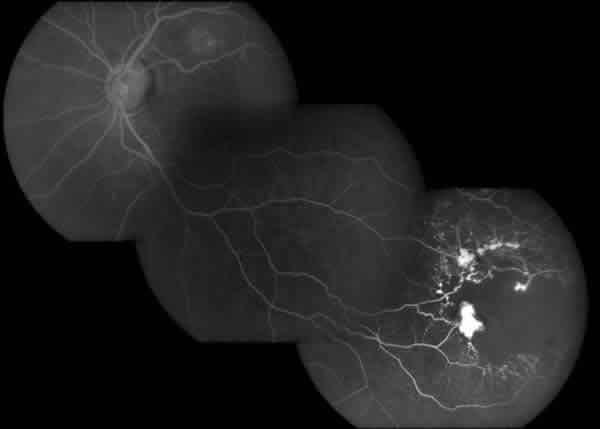

Mujer de 58 años que acudió de urgencia por miodesopsias OI de 12 horas de evolución. A la exploración oftalmológica presentaba una agudeza visual de 1 sin corrección en ambos ojos con un hemovítreo leve en cuadrante temporal inferior del OI, adyacente a un área con dilatación e isquemia del lecho capilar acompañadas de múltiples dilataciones aneurismáticas rojizas de tamaño variable, muchas saculares, una de ellas de gran tamaño con cierta proliferación glial (figs. 3 y 4). En tiempos tardíos de la angiografía se constataba extravasación de contraste. Se realizó fotocoagulación del área de las telangiectasias con ablación de las lesiones aneurismáticas, manteniendo una agudeza visual de la unidad (fig. 5).

Fig. 4. AFG: Dilatación y tortuosidad de los vasos retinianos con múltiples ectasias vasculares alrededor de un área de isquemia capilar.